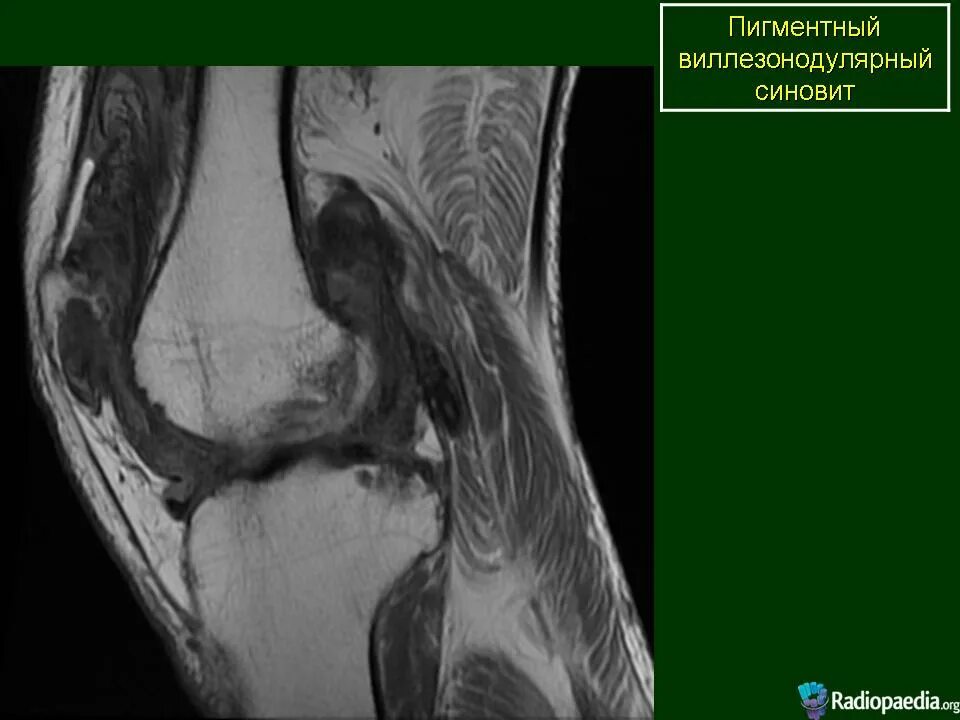

Пигментный виллонодулярный синовит